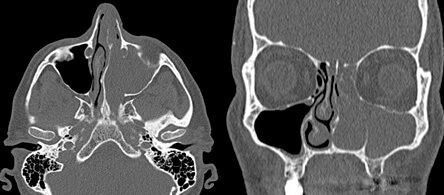

В диагностике инвертированных папиллом ключевое место занимают лучевые методы исследований

- компьютерная томографии

Ценность КТ – материалов состоит в возможности точной оценки границ опухоли, что позволяет определить стадию процесса и тактику дальнейшего ведения больного. МР-данные позволяют дифференцировать активный воспалительный процесс в пазухах от фиброзной и рубцово-измененной ткани. Введение контрастного препарата повышает яркость свечения воспаленной слизистой оболочки.